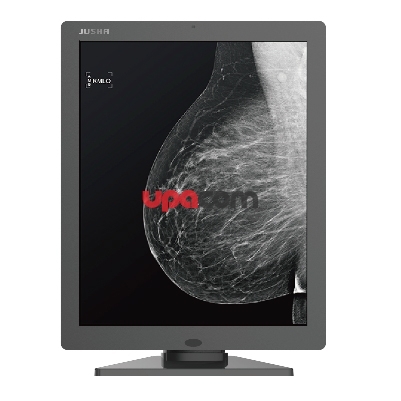

Отображение рентгеновских изображений и изображений в поперечном разрезе является основной задачей RX250. Благодаря характеристической кривой DICOM GSDF она может точно отображать радиологические экспозиции.

Медицинский монитор RX250 RadiForce

Отображение рентгеновских изображений и изображений в поперечном разрезе является основной задачей RX250. Благодаря характеристической кривой DICOM GSDF она может точно отображать радиологические экспозиции.

Безопасное качество изображения благодаря совместимости AAPM / Euref / DIN

Свойства дисплея, в частности яркость и контраст, подходят для создания систем рендеринга изображений, соответствующих стандарту DIN 6868-157. Характеристика DICOM GSDF уже точно настроена на заводе. Это означает, что оттенки серого соответствуют друг другу, что жизненно важно для диагностики.